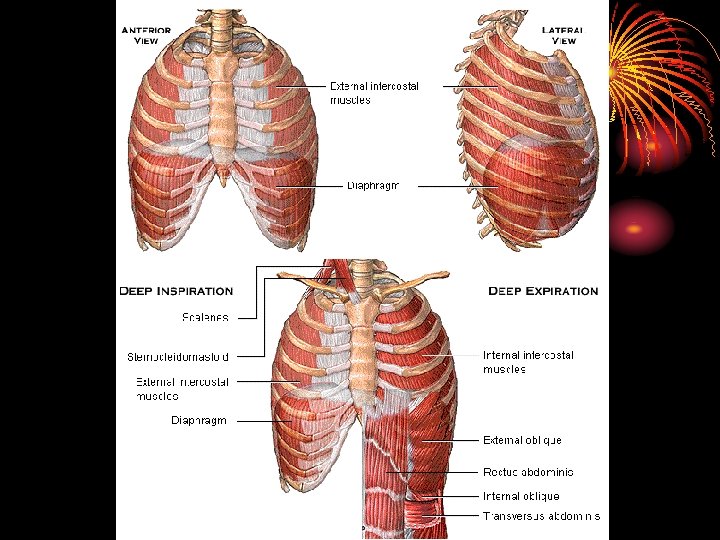

Mechanics of respiration • Respiratory rate in adults 12 -15/min. • 500 ml in each breath, 6 -8 l/min. • 250 ml of O 2 taken, 200 ml CO 2 expired/min. Inspiration: Inspiratory muscles: 1. Diaphragm: vertical axis, increase thoracic cavity by 75% in quiet respiration.

2. External intercostal muscles: anteroposterior diameter, 10% only. 3. Accessory inspiratory muscles: act in forcible respiration: scalene and sternocleidomastoid muscles. Mecahnics Contraction of insp. muscles decreases intrapleural pressure from – 2. 5 mm Hg to – 6 mm. Hg : by increasing the thoracic cavity the lungs will move with the thoracic cage as the parietal and visceral pleurae are in contact, the pressure in airways decreases, leading to entry of air from outside.

• In forcible insp. intrapleural pressure reaches – 30 mm Hg Expiration: • Passive process due to elastic recoil of insp. muscle and lungs leading to increased press. in airways and outflow of air. • Accessory expiratory muscles work in forced expiration: abdominal muscles and internal intercostal.